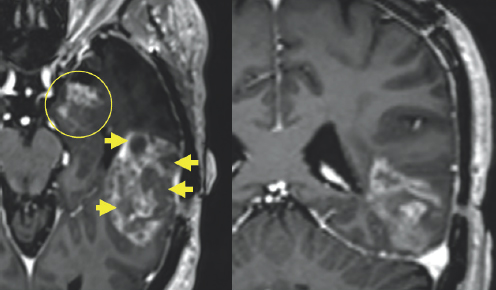

(Left) Gray colored variations are enclosed by black and white outlines. To the right of the center of the image, there is a white blob with gray variations highlighted by four yellow arrows on the left side of the blob. (Right) Gray variations are enclosed by black and white outlines. There is a white blob with variations of gray surrounding it on the right side of the image. This blob is highlighted by three yellow arrows.

FIGURE 2.4 Brain MRI after surgery. Imaging shows post-treatment and post-operative changes from resection of the left temporal tumor. There are patchy and irregular areas of abnormal enhancement within the medial margin of the surgical cavity that appear bright after being injected with IV contrast (yellow arrows), uncertain for residual tumor versus post-treatment changes.

(Left) A variation of gray colored structures are surrounded by a black and white outline. On the top right of the image, there is a small white blob highlighted by a yellow circle. (Right) A variation of gray colored structures are surrounded by a large black and white outline. There is a small white blob in the center of the image highlighted by a red circle. There are two additional gray blobs with white coloration on them highlighted by two yellow arrows on the right side of the image.

FIGURE 2.5 Brain MRI after surgery. Imaging shows post-treatment and post-operative changes from resection of the left temporal tumor. There is interval decreased abnormal patchy enhancement within the medial left temporal lobe (yellow circle) and stable tiny enhancing lesion within the left aspect of the midbrain (red circle), which are also uncertain for residual tumor versus post-treatment changes.

White and light gray color variations are enclosed by a black and dark gray outline. There is significant white coloration on the right side of the image which is highlighted by a yellow oval.

FIGURE 2.6 Brain MRI after surgery. There is surrounding signal alteration on the MRI sequence image similar to the MRI before the surgery, which is nonspecific but likely represents swelling (yellow oval).

Initially, after the treatment, there was no obvious progression in his symptoms, but by mid-May of that same year, there was a dramatic decline in his condition (Fig. 2.4–2.7). Several concerning transient symptoms appeared, including confusion, lethargy, and significant memory loss, which impacted his compliance with his treatments and caused him to sometimes forget his regimen.